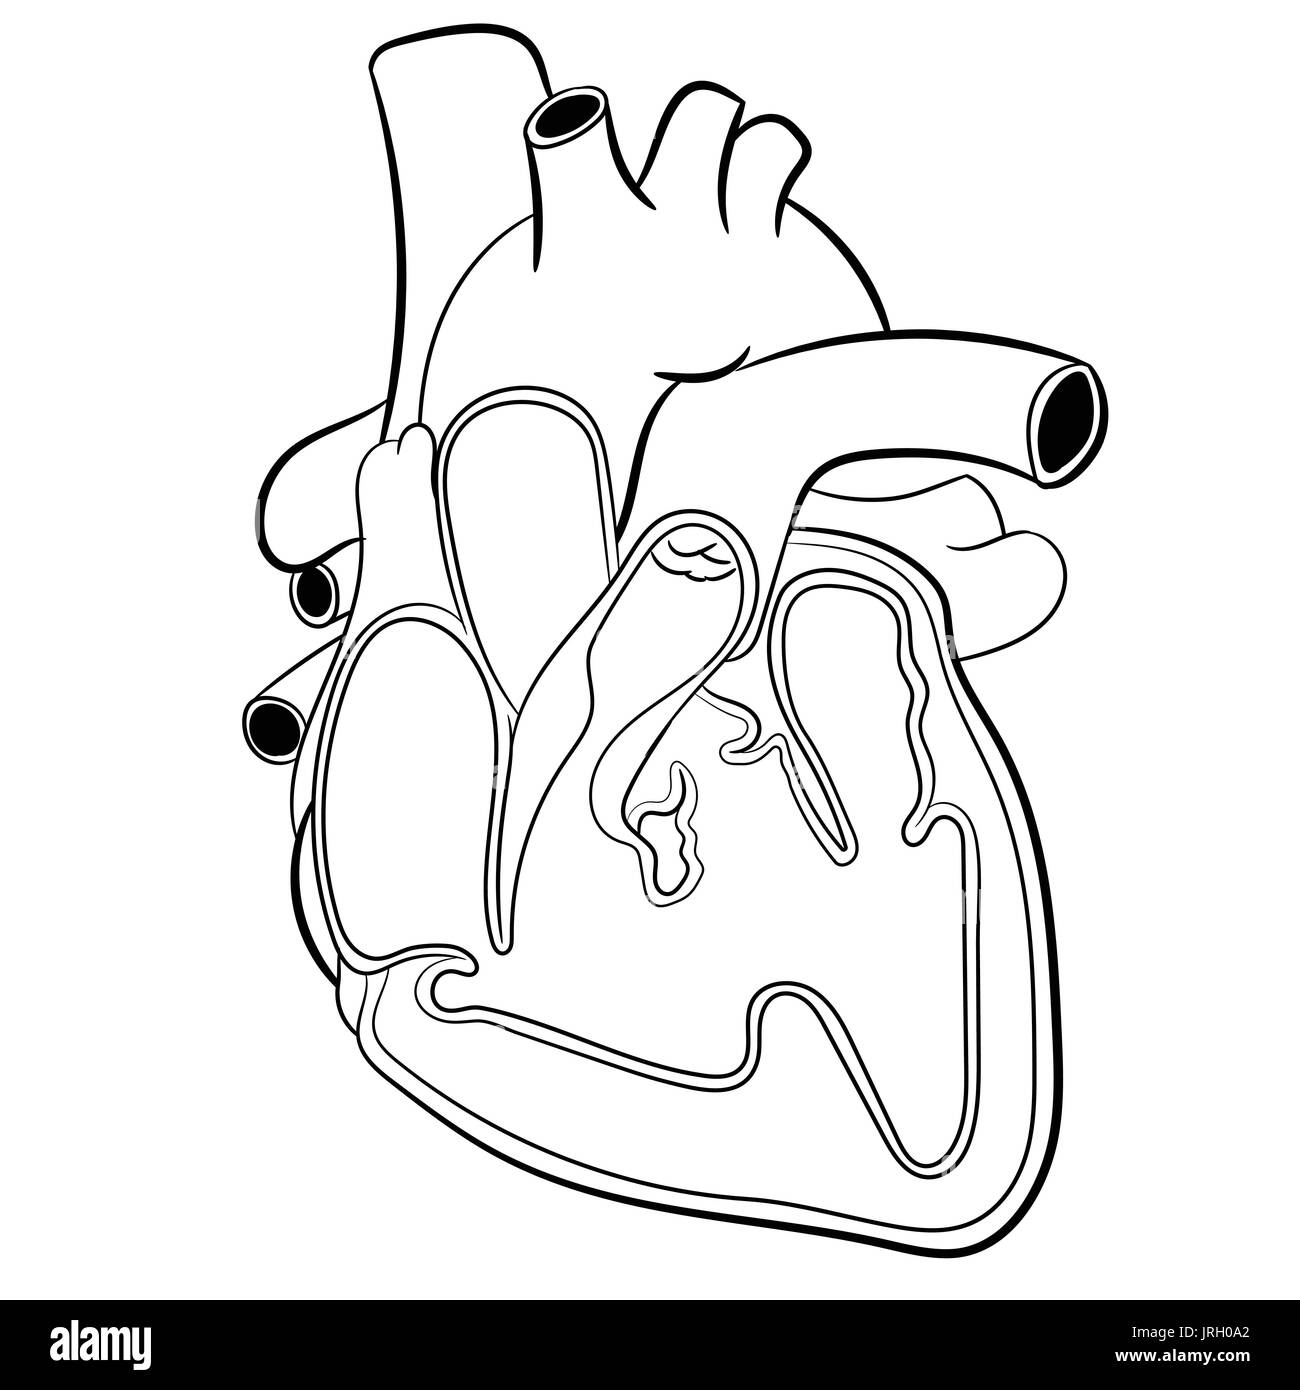

Anatomical Human heart hand drawn. Medicine educational Vector illustration. Stock Vectorhttps://www.alamy.com/image-license-details/?v=1https://www.alamy.com/anatomical-human-heart-hand-drawn-medicine-educational-vector-illustration-image152193498.html

Anatomical Human heart hand drawn. Medicine educational Vector illustration. Stock Vectorhttps://www.alamy.com/image-license-details/?v=1https://www.alamy.com/anatomical-human-heart-hand-drawn-medicine-educational-vector-illustration-image152193498.htmlRFJRH0A2–Anatomical Human heart hand drawn. Medicine educational Vector illustration.